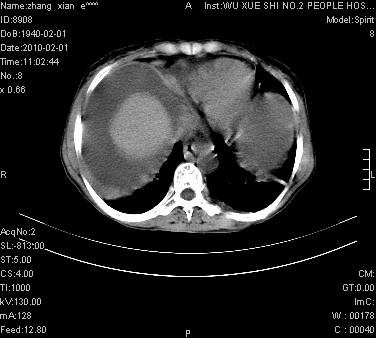

标题: CT24434:70岁 女 腹胀,腹水原因待查 [打印本页]

标题: CT24434:70岁 女 腹胀,腹水原因待查

大量腹水,脾脏囊性占位,子宫颈占位,右侧腹股沟淋巴结肿大,建议+c,先查妇科。

腹盆腔大量积液,子宫增大,子宫颈增大外形不规则,内见低密度影,膀胱后壁显示不清,右腹股沟肿大淋巴结,脾脏囊性占位,子宫颈占位,子宫颈癌?建议增强。

子宫、宫颈占位?转移性腹水?肝性腹水?脾脏囊性占位,囊肿?血管瘤?淋巴瘤?

考虑:1、腹膜转移,大量腹水;

2、脾占位性病变;

3、左侧卵巢占位性病变,建议增强进一步检查。

大量腹水,右肾、脾囊肿可能性大          考虑左侧附件区占位,建议增强